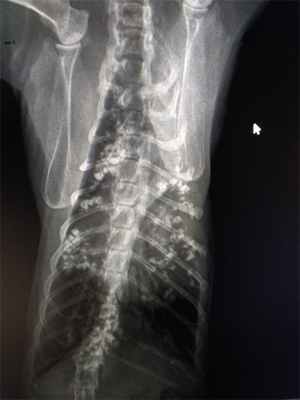

По данным анамнеза и осмотра животного было принято решение провести рентгенологическое обследование грудной полости.

По Rtg (рис 1,2) выявлено множество рентгеноплотных/контрастных очагов в грудной полости. Размер и форма тени сердца была не изменена

После общения с владельцами выяснилось, что накануне до начала кашля кот отказывался от корма, после принудительного кормления у него сразу была рвота. Симптомы продолжались 3 дня, а на 4-ые сутки владельцы обратились в стороннюю клинику, где диагностировали инородное тело кишечника. Провели лапаротомию и удалили пуговицу из кишки.

После операции через рото-пищеводный зонд дали сульфат бария с целью контрастирования кишечника и выявления сохранения возможной непроходимости. Провели два рентгеновских снимка с интервалом в 6 часов, по результатам которых не было выявлено наличие непроходимости желудочно-кишечного тракта.

Пациенту был поставлен окончательный диагноз - аспирационная пневмония.